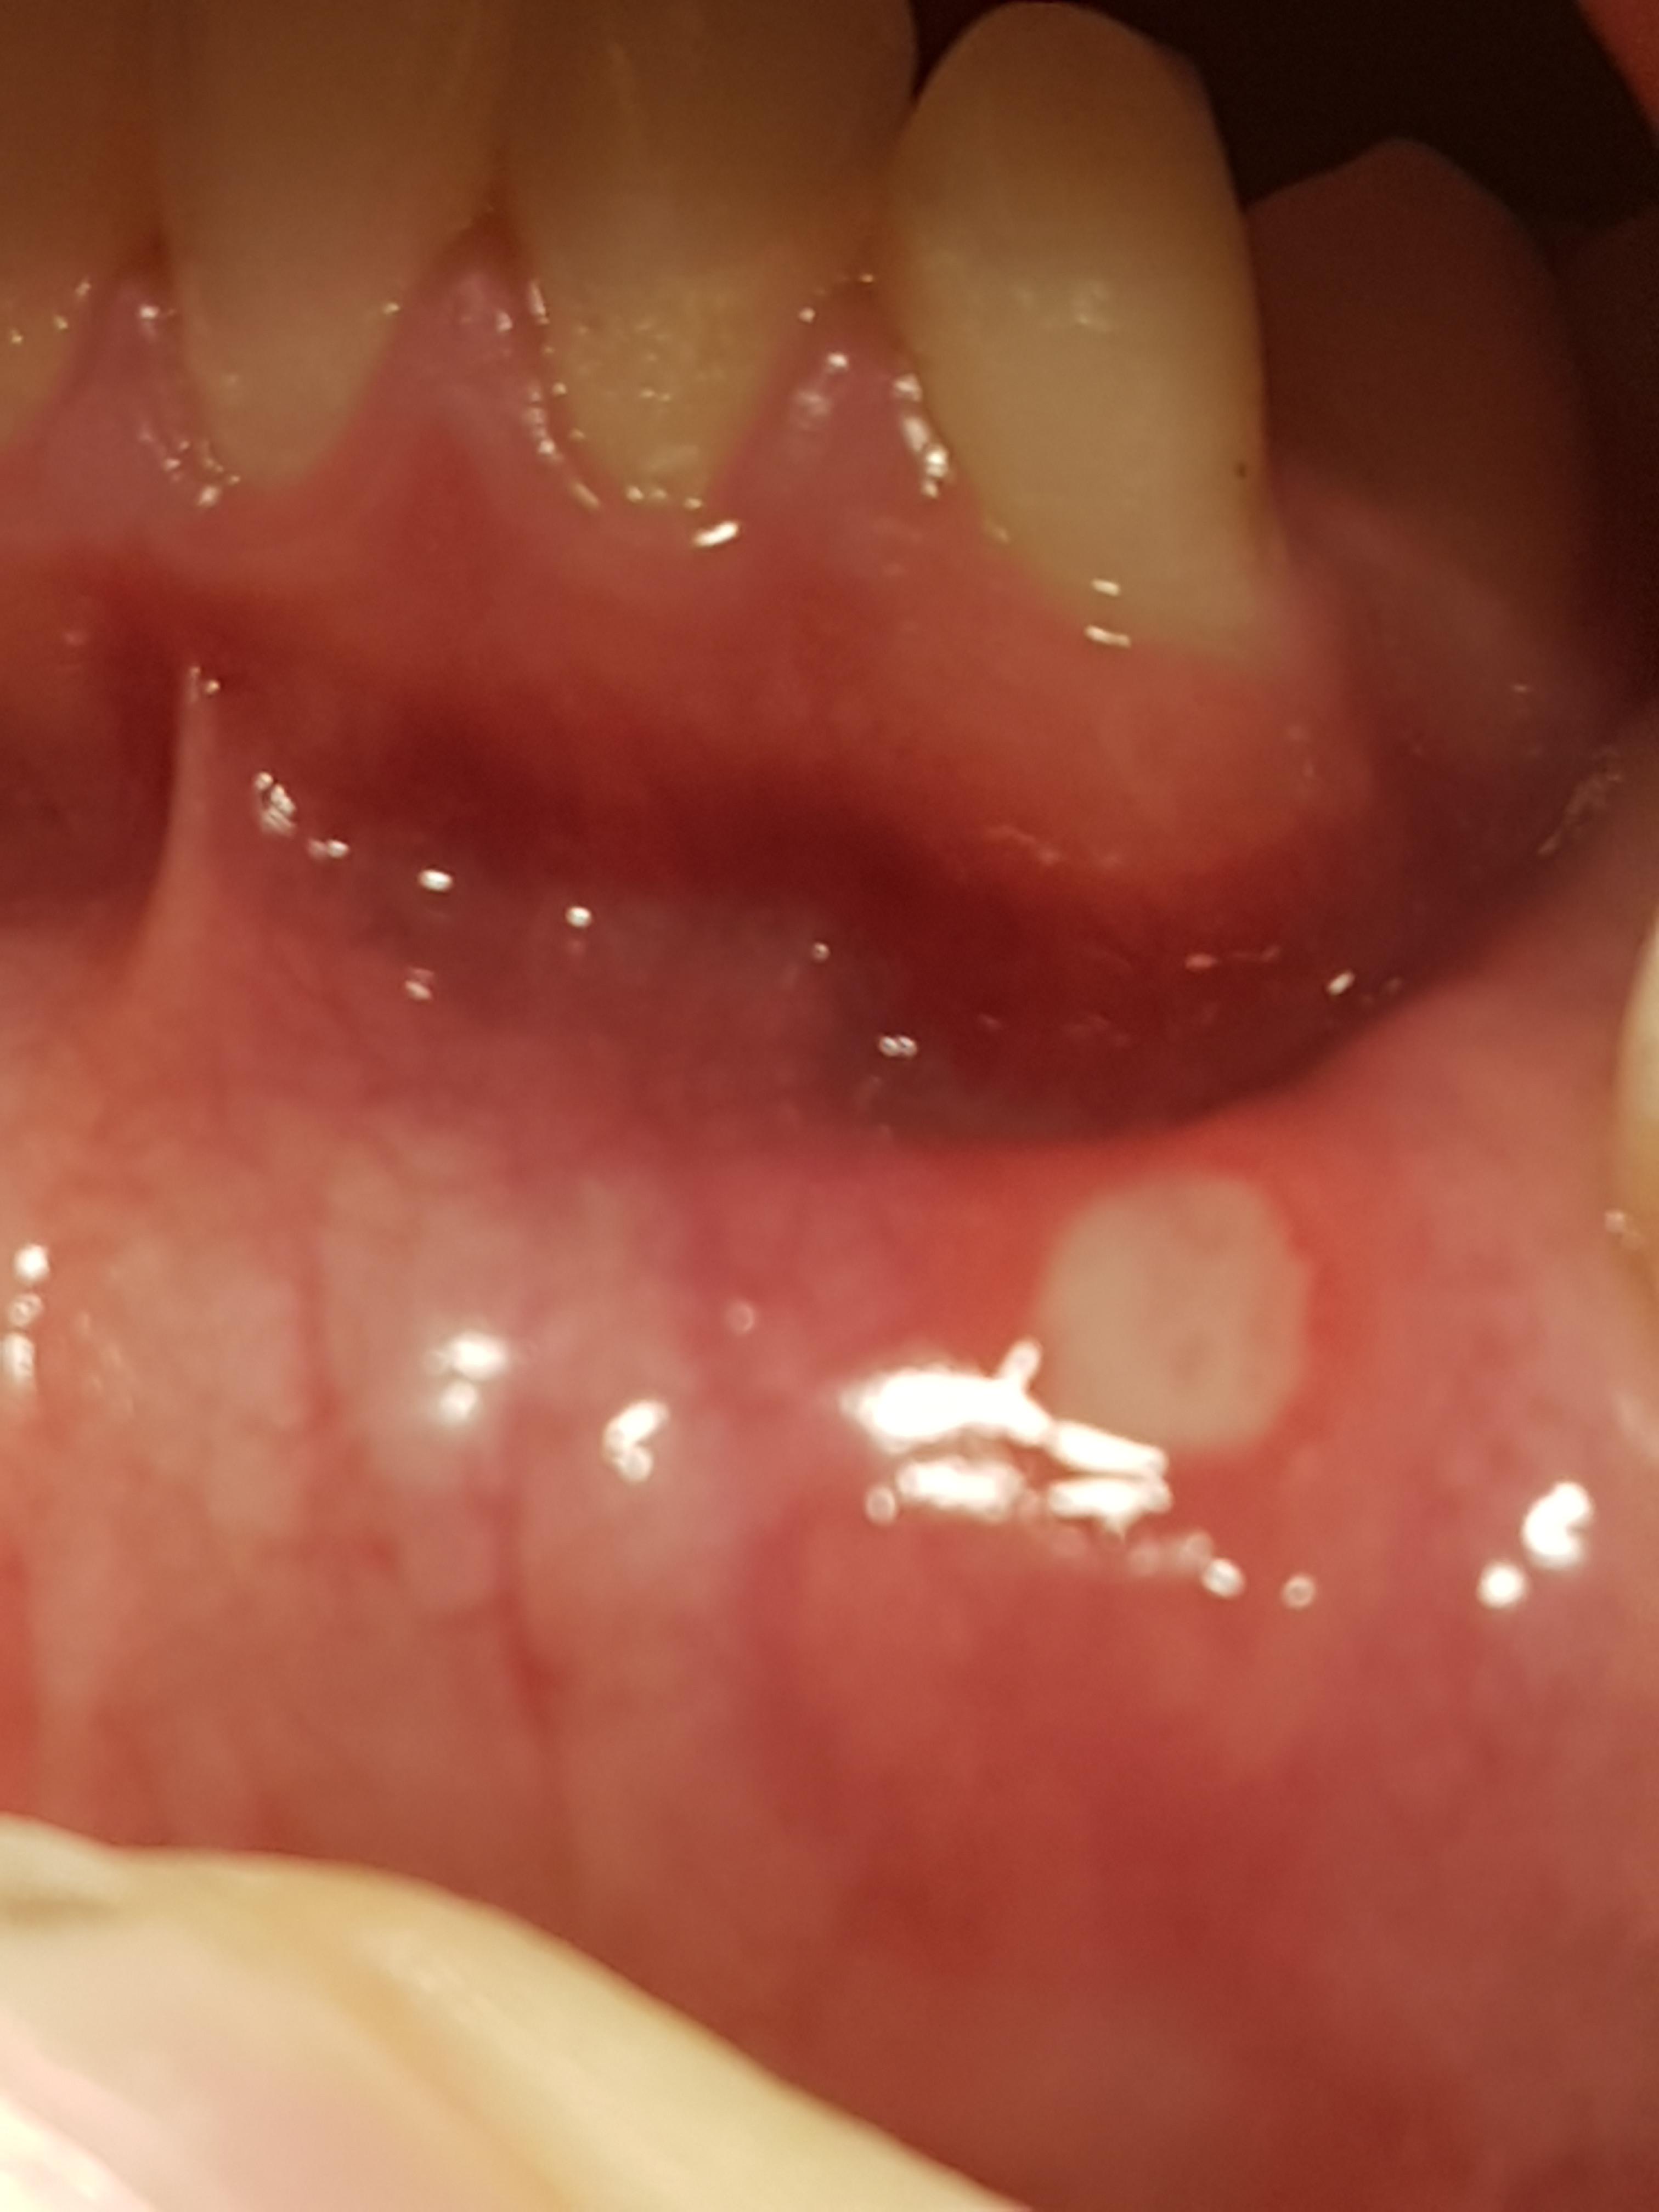

Zunge hat zahnabdruck? (Zähne) www.gutefrage.netWeisse Stelle Im Mund? (Gesundheit Und Medizin)

Weisse Stelle im mund? (Gesundheit und Medizin) www.gutefrage.netmund weisse medizin